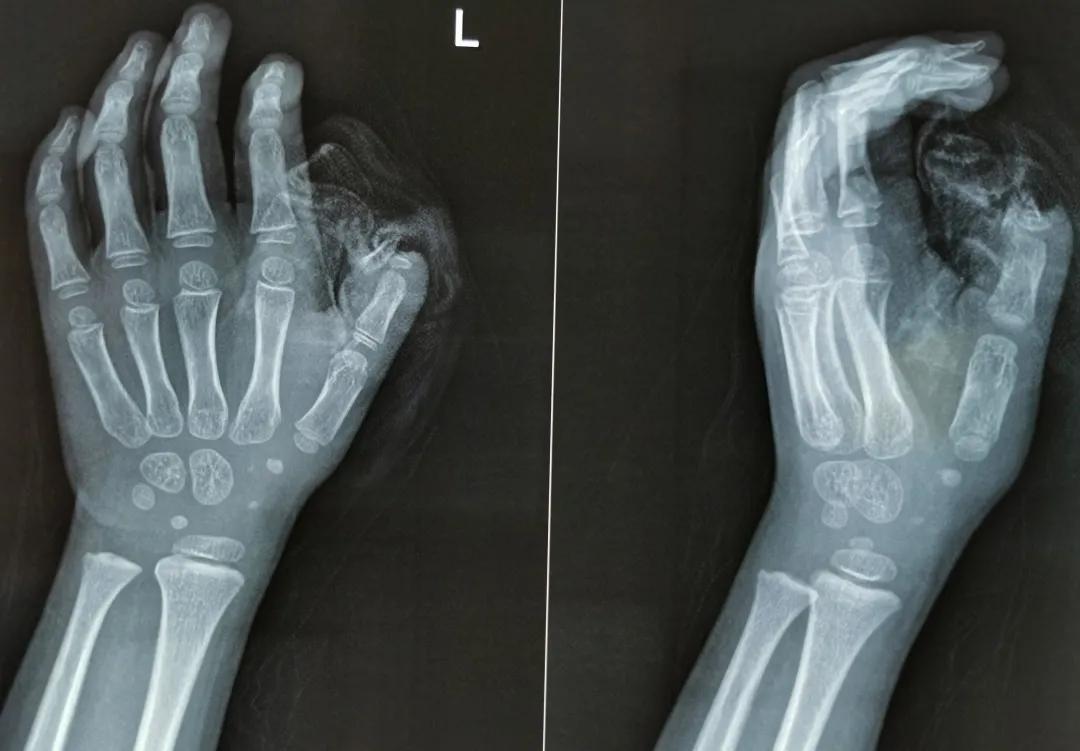

辗转来到杭州市红十字会医院,急诊医生接诊后发现,小珍珍的拇指损伤严重,骨头露在外面的部分很多,有骨折情况,手指弯曲畸形,于是请骨科主任医师韩贵和立即安排手术。

韩医师认为,患儿拇指指骨末节缺损,周围皮肤挫伤严重,无法原位缝合,可能需要截取远端指骨。截指手术是一种致残手术,但拇指占手指功能的50%,失去大拇指对这么小的孩子来说,无疑是难以承担的。如何最大程度恢复小女孩拇指的美观及功能是医生及家长共同关注的问题。

最终,韩医师决定,将珍珍断裂的骨头复位,用克氏针固定,然后将残余的拇指暂时移植至肚皮,等肚子上的皮肤成功种植到手指上后再行二次修复。这样,小女孩的拇指长度基本可以完整保留,既解决了皮肤缺损的问题,还能够恢复拇指的运动功能。

图:手术室内,

医生将患儿的断指与腹部皮瓣连接